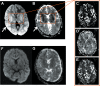

The mechanisms underlying the rapidly reversible brain swelling described in patients with cerebral malaria (CM) are unknown. Using a 1.5-Tesla (T) magnetic resonance imaging (MRI) scanner, we undertook an observational study in Rourkela, India, of 11 Indian patients hospitalized with CM and increased brain volume. Among the 11 cases, there were 5 adults and 6 children. All patients had reduced consciousness and various degrees of cortical swelling at baseline. The latter was predominately posterior in distribution. The findings on diffusion-weighted imaging (DWI) and apparent diffusion coefficient (ADC) maps were consistent with vasogenic edema in all cases. Reversibility after 48 to 72 h was observed in >90% of cases. DWI/ADC mismatch suggested the additional presence of cytotoxic edema in the basal nuclei of 5 patients; all of these had perfusion parameters consistent with vascular engorgement and not with ischemic infarcts. Our results suggest that an impairment of the blood-brain barrier is responsible for the brain swelling in CM. In 5 cases, vasogenic edema occurred in conjunction with changes in the basal nuclei consistent with venous congestion, likely to be caused by the sequestration of Plasmodium falciparum-infected erythrocytes. While both mechanisms have been individually postulated to play an important role in the development of CM, this is the first demonstration of their concurrent involvement in different parts of the brain. The clinical and radiological characteristics observed in the majority of our patients are consistent with posterior reversible encephalopathy syndrome (PRES), and we show for the first time a high frequency of PRES in the context of CM. IMPORTANCE The pathophysiology and molecular mechanisms underlying cerebral malaria (CM) are still poorly understood. Recent neuroimaging studies demonstrated that brain swelling is a common feature in CM and a major contributor to death in pediatric patients. Consequently, determining the precise mechanisms responsible for this swelling could open new adjunct therapeutic avenues in CM patients. Using an MRI scanner with a higher resolution than the ones used in previous reports, we identified two distinct origins of brain swelling in both adult and pediatric patients from India, occurring in distinct parts of the brain. Our results support the hypothesis that both endothelial dysfunction and microvascular obstruction by Plasmodium falciparum-infected erythrocytes make independent contributions to the pathogenesis of CM, providing opportunities for novel therapeutic interventions.